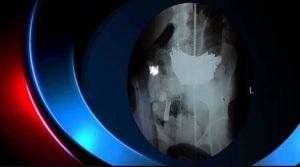

كشف مستشفى الحسين العام عن نجاحه بـ إستخراج كيلو غرام من (المسامير الحديدية) من معدة مريضة تبلغ من العمر 18 عام في السماوة.

وأشار المستشفى، إلى ان المريضة تعاني من مرض نفسي، وإبتلعت هذه الأجسام، قبل حوالي شهر، وهو ما أدى إلى حدوث نزيف في المعدة نتيجة تمزق جدار المعدة.